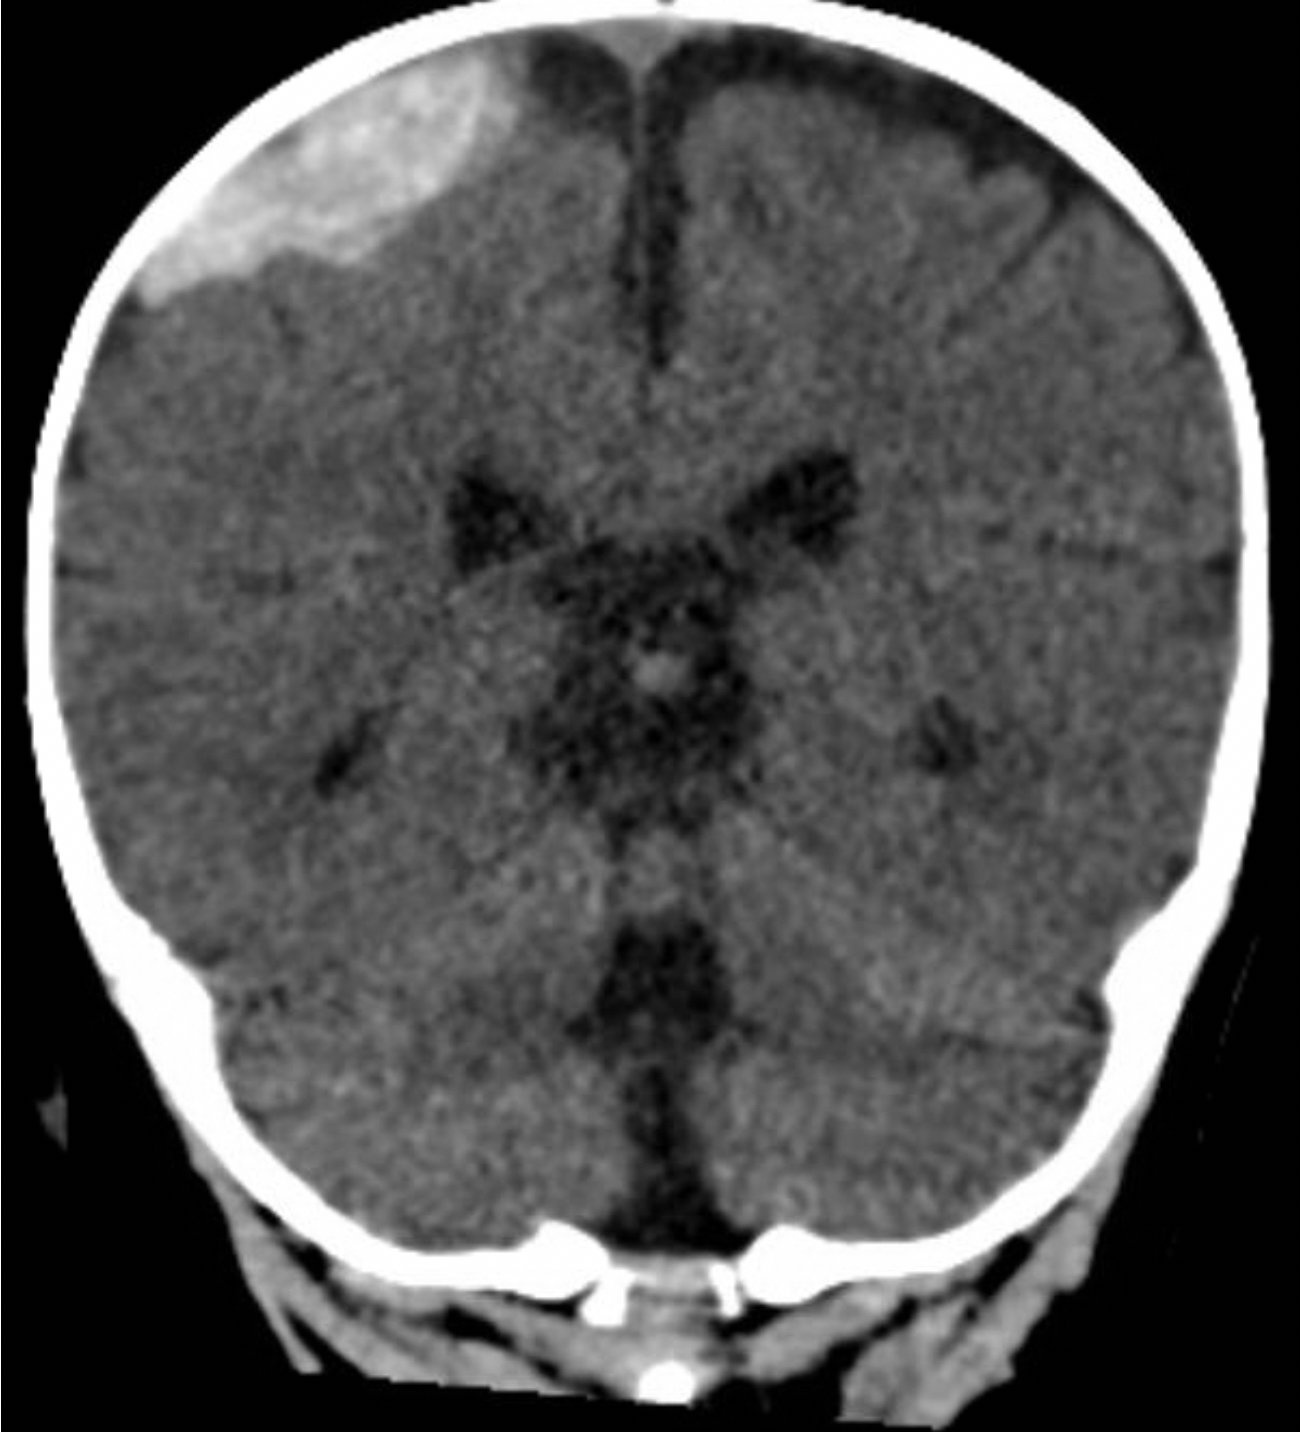

A computed tomography (CT) scan of the head without contrast was obtained out of concern for intracranial pathology due to the patient’s young age and the witnessed focal seizure. The CT showed a 4.2 x 1.2 x 1.5 cm acute extra-axial intracranial right frontoparietal hemorrhage favoring epidural over subdural hemorrhage given its lenticular shape. There was no underlying fracture, herniation or midline shift identified.

Given the concern for non-accidental trauma in this nonmobile child with no history of trauma, pediatric surgery and neurosurgery were consulted and further bloodwork was obtained, revealing elevated partial thromboplastin time (PTT) and a normal prothrombin time (PT). Further work-up led to a diagnosis of severe hemophilia A. He was managed non-operatively with factor VIII infusions to achieve normal factor levels. He remained neurologically stable without further seizure activity during his hospitalization. A skeletal survey showed no fractures. He received levetiracetam for 6 months and had no neurological deficits.